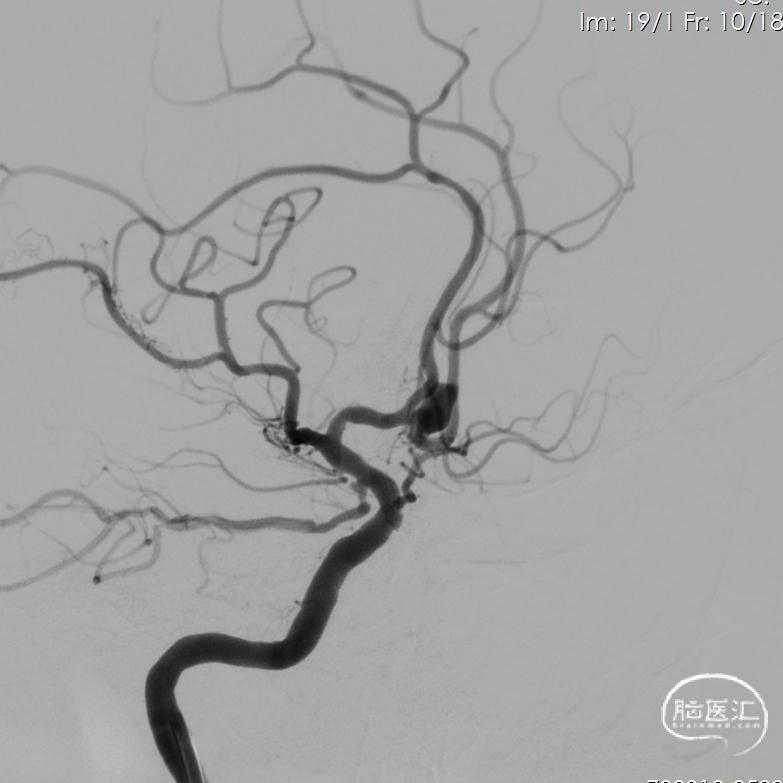

14、栓塞后造影。

栓塞后正位造影

13、支架置入后左侧大脑前动脉血流好转。

术后给予替罗非班静脉泵入,术后第二天进行MRA。